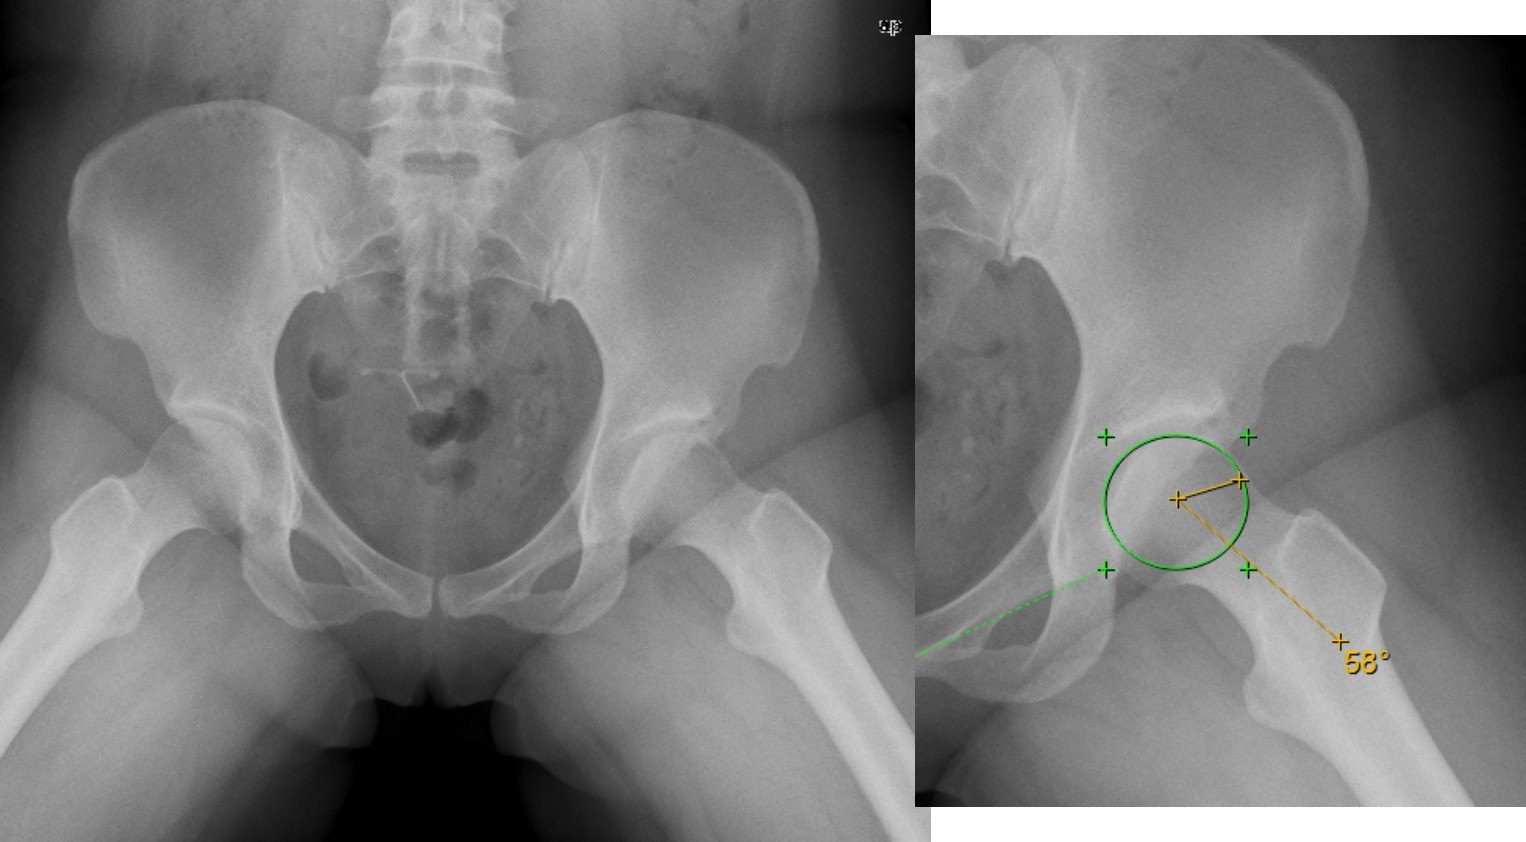

石X,女性,38岁,主诉:左髋反复间断疼痛半年余. 半年前长时间行走出现左髋酸痛不适感,呈间歇性刺痛,位于髋关节深部,休息5-10分钟可缓解,无关节弹响,无绞锁,无下肢放射疼痛及麻木。未予以特别处理。之后左髋经常出现行走酸胀感,活动后加重,症状无法缓解来就诊。查体: 正常步态;屈髋疼痛(+), 腹股沟区压痛(-),大转子压痛(-),ROM:屈髋/后伸/外展/外旋/内收/内旋 110/10/40/30/30/20, FAIR(+), FAER(-),4字征(-),贴床面(2拳), 余(—)。

术前检查 X线 CT和单髋MRI

X线、CT检查能排除髋关节退变、发育不良、骨关节炎、髋关节撞击等骨性异常结构,但不能很好显示软组织病变,因此不能诊断髋臼盂唇损伤。MR检查具有较好的软组织对比性,分辨率较高,可多方位和多序列的成像,可以直接显示髋臼盂唇的形态和信号。MR检查又有MRI(MR Imaging)和MRA(MR Arthrography)之分,后者又可分为直接关节造影(Direct MR Arthrography )和间接关节造影(Idirect MR Arthrography)。